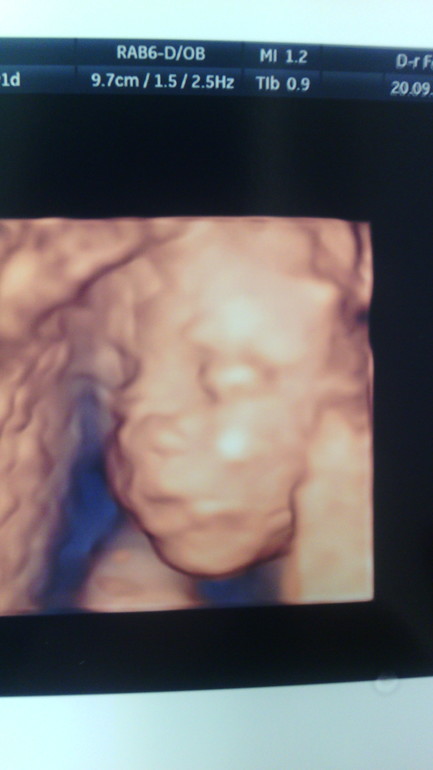

Ну и подтвердили нам нашу девочку!

И фоточки:

И да! Сегодня впервые наша доченька дала о себе знать: такие ощутимые пиночки почувствовала!!! 21 неделя и 5 дней!